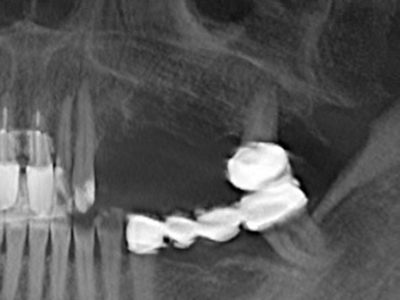

Fig. 17a: immagine TC di un'osteotomia con promozione di crescita immediatamente adiacente a...

Fig. 17b: dotto dell'alveolo dentale con irritazione del nervo (vista laterale e coronale).

Fig. 18: preparazione di una copertura corticale con sega piezoelettrica per osso (Piezomed, W&H).

Fig. 19: sito chirurgico dopo neurolisi e rimozione dell'osteoma.

Fig. 20: la copertura ossea rimossa viene riadattata e fissata con una vite per osteosintesi (KLS Martin, Tuttlingen).